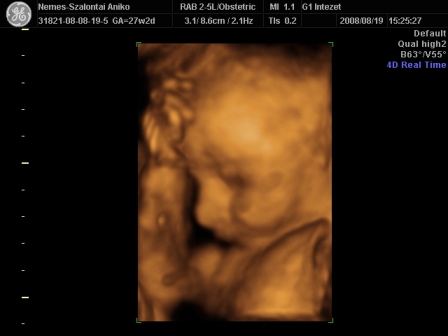

Én Óbudán a G1 intézetben voltam 4D-n. Régen ők voltak a Schöpf-Méreiben. Nagyon-nagyon kedvesek voltak. Nem kaptam letolást, mert késtünk sajnos a dugó miatt. Mondták telefonban, hogy ne idegeskedjek, csak menjünk :D .

Egy nagyon kedves hölgy vizsgált. Mindent megtett, hogy a lehető legjobb képet tudja csinálni a piciről. Nem volt könnyű dolga, mert végig háttal volt, a pofikája előtt volt a köldökzsinór, a két keze és az egyik talpa :lol: . Tornász lesz a gyerek :D . Viszont a fiússágát rögtön megmutatta. Összesen fél órás volt a vizsgálat. A picur méretei teljesen megfelelnek annak, ahány hetes vagyok. Eszerint nov. 9. és 16. között születik. Nem tudom, hogy a saját dokim, honnan szedett 20-át? Mindegy, úgyis akkor jön, amikor jönnie kell. A súlya a picinek 1103 g :) . Jó a szívhang és a köldökzsinór véráramlása is.

Készült DVD az egész vizsgálatról. 4 fényképet kinyomtattak, amit mi választottunk ki. És feltöltötték a honlapjukra az összes képet, amit egy kapott kóddal megnézhet bárki 30 napig. Így a távoli-külföldi rokonok is rögtön láthatják a bébit :).

Szóval teljesen elégedett voltam. Nekem a vizsgálat (hála a babaszobának) ingyenes volt, amúgy 13e Ft.

Ez már tuti, hogy fiú

Kis pofikája I.

Kis pofikája II.

És a tornász pozíció